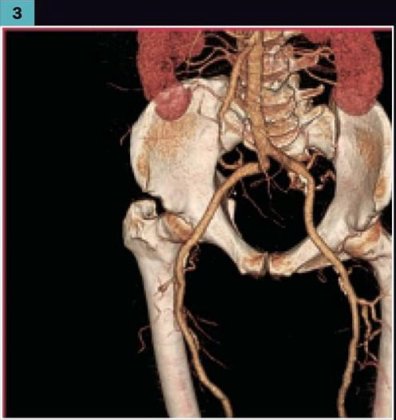

2004 GE LIGHTSPEED 16 SLICE CT SCANNER. Detector channels: 16 x 912. Scan Times:360 degrees, 0.5-0.9 and 1,2,3,4. Slice Thickness mm-0.625, 1.25, 2.5, 3.75, 5, 7.5, 10mm. Gantry Tilt: 30 degrees. X-Ray Tube: 6.3 mHu. X-Ray Generator: 53.2 kW, 10-440 mA’s. Spiral Scanning: yes, Max. scan time: 120 seconds, Max. scan volume: 170 cm. Reconstruction time: 0.1667 seconds. Computer CPU-Open architecture (LINUX). Maximun umber of images displayed at once: 16. Archival Storage: 2.3 GB MOD DICOM 3. CT Angiography: Standard (MiP), and DICOM 3.0 Interface-yes. OPTIONAL: CT Simulation and 3-D Package. This system is available soon. Subject to prior sale.

The used GE Lightspeed RT 16 CT machine is considered one of the world’s leading CT scanners for cancer care. The GE Lightspeed RT 16 CT scanner is a wide-bore system that is easy to operate and features predefined protocols that allow your to perform a wide variety of applications fast and efficiently while delivering exceptional comfort to your patients. This used CT scanner has the power to tackle 3D and 4D imaging as well as display different images simultaneously in real-time..

The refurbished Lightspeed RT 16 is known to be easy-to-use and its ability to display multiple 3D and 4D images simultaneously. The Lightspeed 16 radiotherapy CT is also popular because of its wide-bore opening of 80cm.